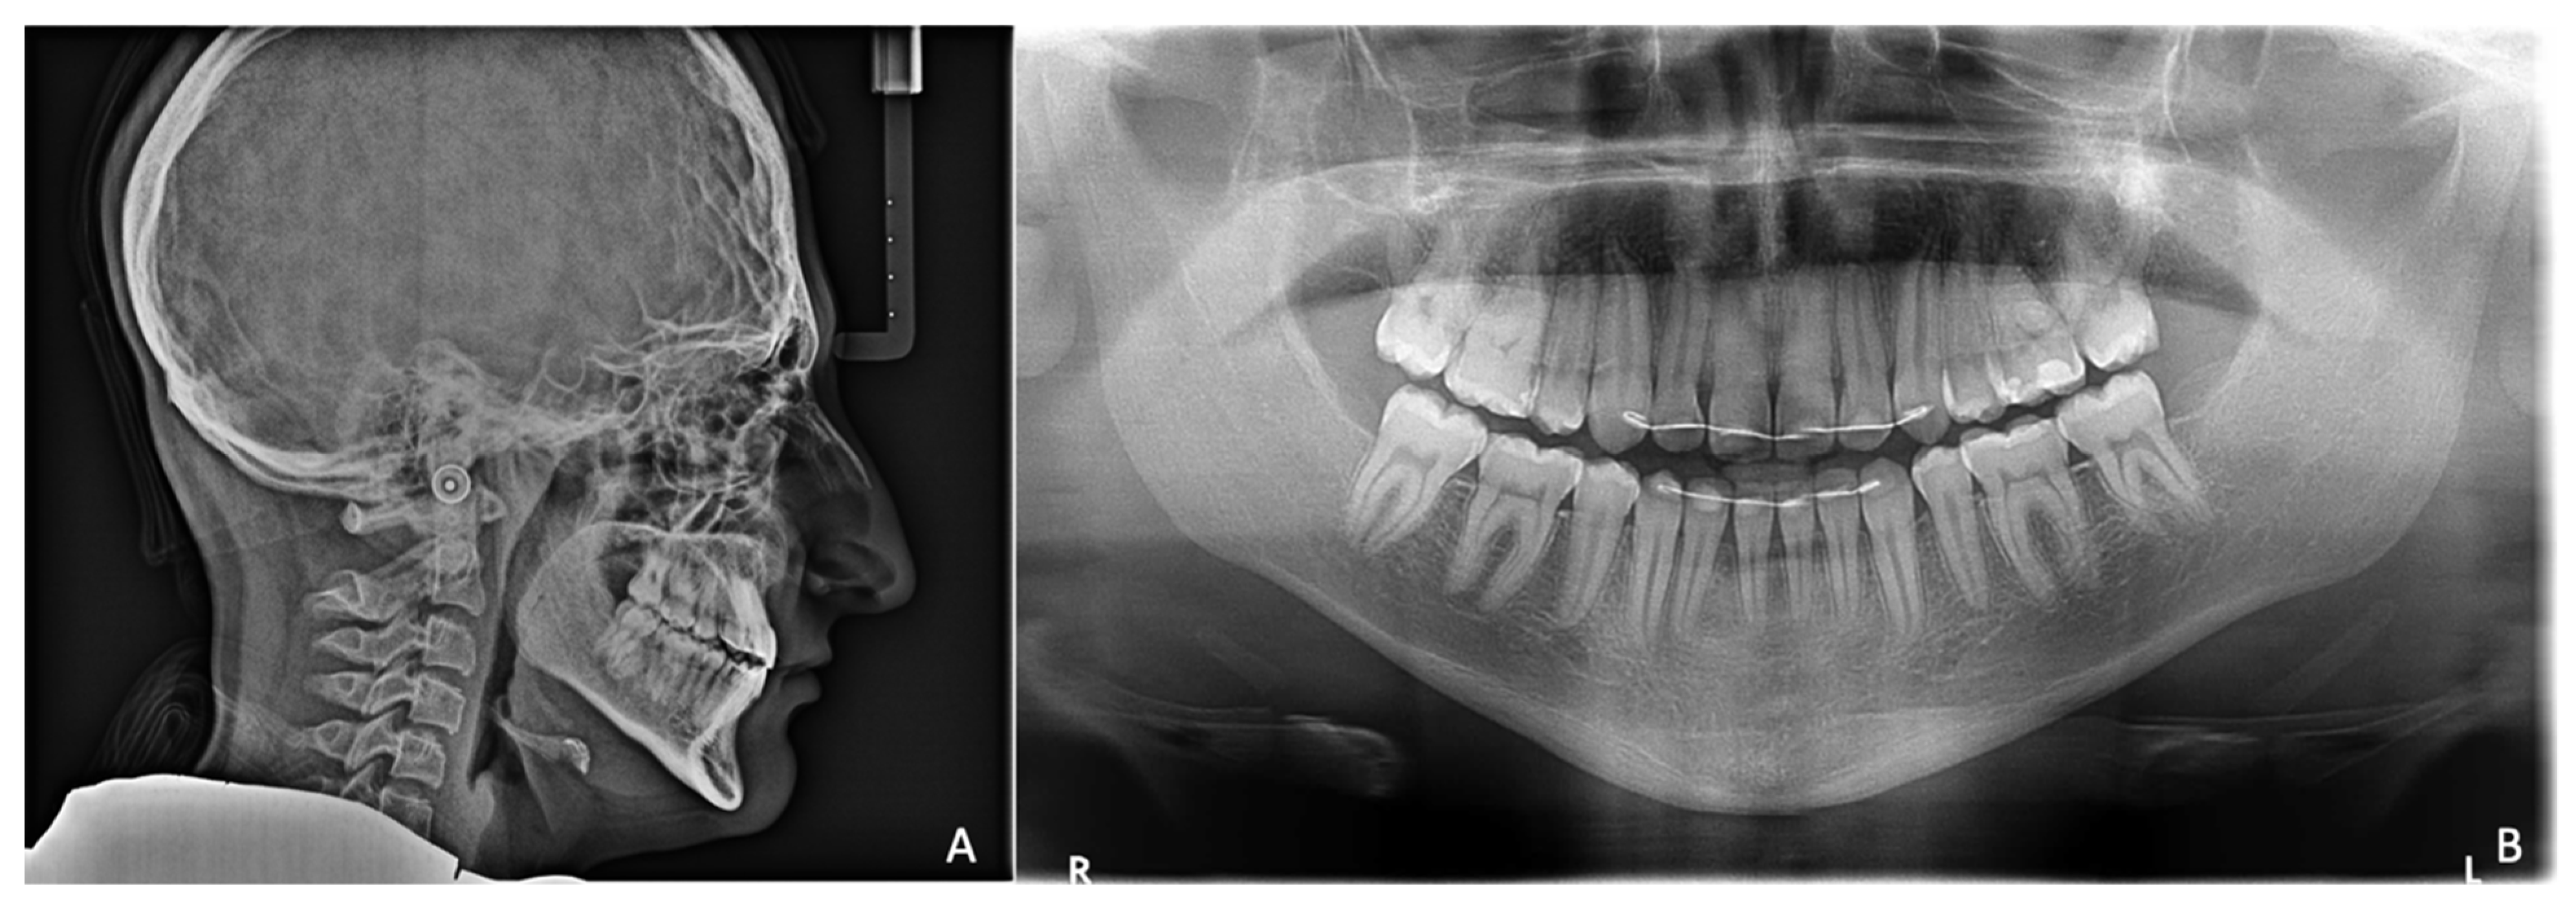

A “copper beaten skull” was evident upon radiographic examination (Figure 2A). An MRI of the skull showed overcrowding due to premature suture synostosis, indicating a mismatch between the volume of the cerebellum and that of the posterior fossa of the skull. Well-developed lateral cerebral ventricles showed that no threatening intracranial pressure was present.

Extraorally, the typical Crouzon syndrome features of brachycephalus, exophthalmos, and hypertelorism were notable. In profile view, the underdevelopment of the midface with absent zygomatic prominence was evident (Figure 3). Intraorally, an early mixed dentition with pronounced crowding and complete loss of space for the upper permanent canines was observed. The maxilla appeared narrow with a high palatal vault without a cleft palate (Figure 3). The extreme mesial–basal jaw relationship came with a WITS appraisal of −18.9 mm, an extremely retrognathic maxilla, and a minor retrognathic mandible (Figure 2A). The need for treatment was manifested intraorally by a more than a full-step class III malocclusion. The patient showed an anterior and left-sided crossbite, and a tendency towards an open bite (Figure 3). Radiographically, impaction of the maxillary canines was evident (Figure 2B).

Figure 2. Pretreatment radiographs. (A). Lateral cephalogram showing extreme mesial–basal jaw relationship. Prominence of convolutional markings throughout the neurocranium indicates chronic increase in intracranial pressure. (B). Panoramic view of a digital volume tomogram showing impaction of maxillary canines and short skeletal base of micrognathic maxilla.